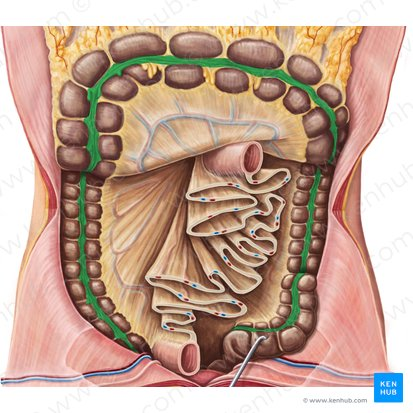

Large intestine / colon

the final section of the digestive tract, responsible for absorbing water and electrolytes and forming feces.

Ascending Colon

Travels upward from the cecum along the right side of the abdomen

Transverse Colon

Travels across the abdomen from right to left.

Descending Colon

Travels downward along the left side of the abdomen.

Sigmoid Colon

An S-shaped curve that connects the descending colon to the rectum.

Rectum

the final section of the large intestine, terminating at the anus, that stores feces before elimination.

Anus

Mesocolon

A fold of peritoneum that attaches the colon to the posterior abdominal wall.

Right Colonic Flexure (Hepatic Flexure)

The bend in the large intestine where the ascending colon becomes the transverse colon, located on the right side of the abdomen.

Ascending Colon

The part of the large intestine that travels upward from the cecum along the right side of the abdomen.

Ileocecal Valve

A sphincter muscle situated at the junction of the ileum and the cecum, which controls the flow of chyme from the small intestine into the large intestine and prevents backflow.

Cecum

A pouch-like structure connected to the junction of the small and large intestines.

Appendix

A small, finger-like pouch attached to the cecum.

Ileum

The final and longest section of the small intestine, which absorbs vitamin B12, bile salts, and any remaining nutrients.

Jejunum

The middle section of the small intestine, where most of the digestion and absorption of carbohydrates, lipids, and proteins occurs.

Transverse Colon

The part of the large intestine that travels across the abdomen from right to left.

Left Colonic Flexure

The bend in the large intestine where the transverse colon becomes the descending colon, located on the left side of the abdomen.

Taenia Coli

Three longitudinal bands of smooth muscle on the outer surface of the large intestine that create haustra.

Descending Colon

The part of the large intestine that travels downward along the left side of the abdomen.

Haustrum